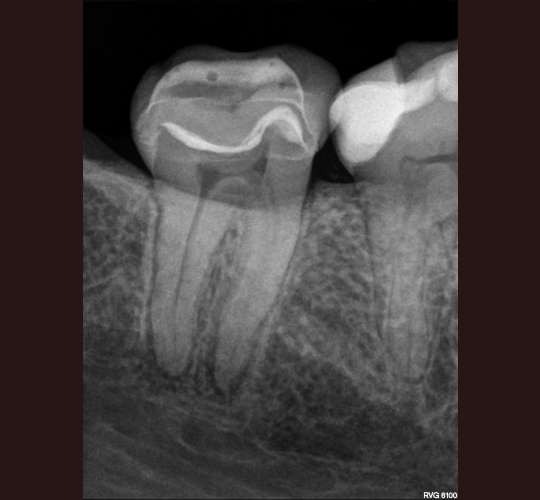

Access Closure: Case #10

When the crown is still intact and in good shape the root canal access opening can be sealed and the crown can be reused. Modern access shape outlines should not overextend and weaken the peri-cervical area. These shapes do not conform to endodontic textbook teachings. These shapes are to be done by qualified microscope using endodontic specialist.

If and only if the doctor feels that sealing your crown can be done to protect your tooth without replacing your crown it may be done in our office by request of your general dentist. If the existing crown is not in excellent shape to prevent leakage into the new root canal your crown may have to be replaced.